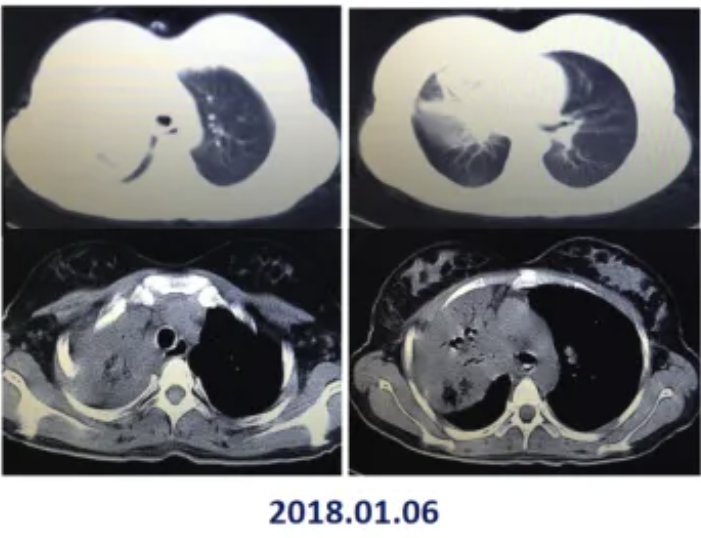

图1: 2018.01.06胸CT

患者2月余前感冒后出现咳嗽,呈阵发性干咳,无略血、发热,自行间断服用感冒药等,咳嗽仍反复,未予重视以及进一步治疗。1月余前咳嗽较前明显加重,夜间明显,一般日常活动后气喘,自感潮热,未测体温,拟就诊于当地医院,入院时突然出现昏迷,立即转诊于某三甲医院,入院后患者神志清醒,测体温39.5℃,考虑为糖尿病酮症酸中毒昏迷,重症肺炎,调整治疗(具体不详)第4日体温正常,之后体温均正常,咳嗽较前好转,咳出白色粘痰,痰量一般,气喘好转。查胸部 CT 提示右肺门增大,右肺上叶部分支气管显示不清,双侧胸腔积液。行胸腔穿刺术,支气管镜检查活检以及治疗。病理:(右肺上叶)送检坏死物,内见真菌。 PAS 染色(+),抗酸染色(-)。第2次支气管镜下见右主支气管管腔覆厚白苔,近隆突峭处见瘘道形成,右肺下叶管腔狭窄镜身无法通过,见新生肉芽组织,较前次比较,覆膜有所变薄,管腔有所缩小,右肺上叶见干酪样坏死,右肺上叶生理盐水灌洗,卡泊芬净保留灌洗,左肺各级支气管粘膜光滑,管腔通畅。入院血常规提示白细胞15x109/L,中性粒细胞12.26X109/L,血小板553X109/L,红细胞3.05X1012/L,降钙素原3.33ng/ mL。治疗后复查血常规提示白细胞8.77X109/L,血小板103X109/L,红细胞3.05X1012/L,降钙素原0.13ng/ mL。G试验, GM 试验阴性。给予甘精胰岛素以及诺和灵 R 控制血糖,并逐步调整剂量,血糖逐渐控制良好。先后给予美罗培南、莫西沙星联合比阿培南,亚胺培南联合万古霉素,伏立康唑、醋酸卡泊芬净抗感染治疗。复查胸部CT提示左肺病变有所吸收,右肺病变减少。为进一步诊治,今来我院门诊就诊,门诊以"支气管狭窄、肺部真菌感染"收入院。病后精神、食欲较差、大小便正常。